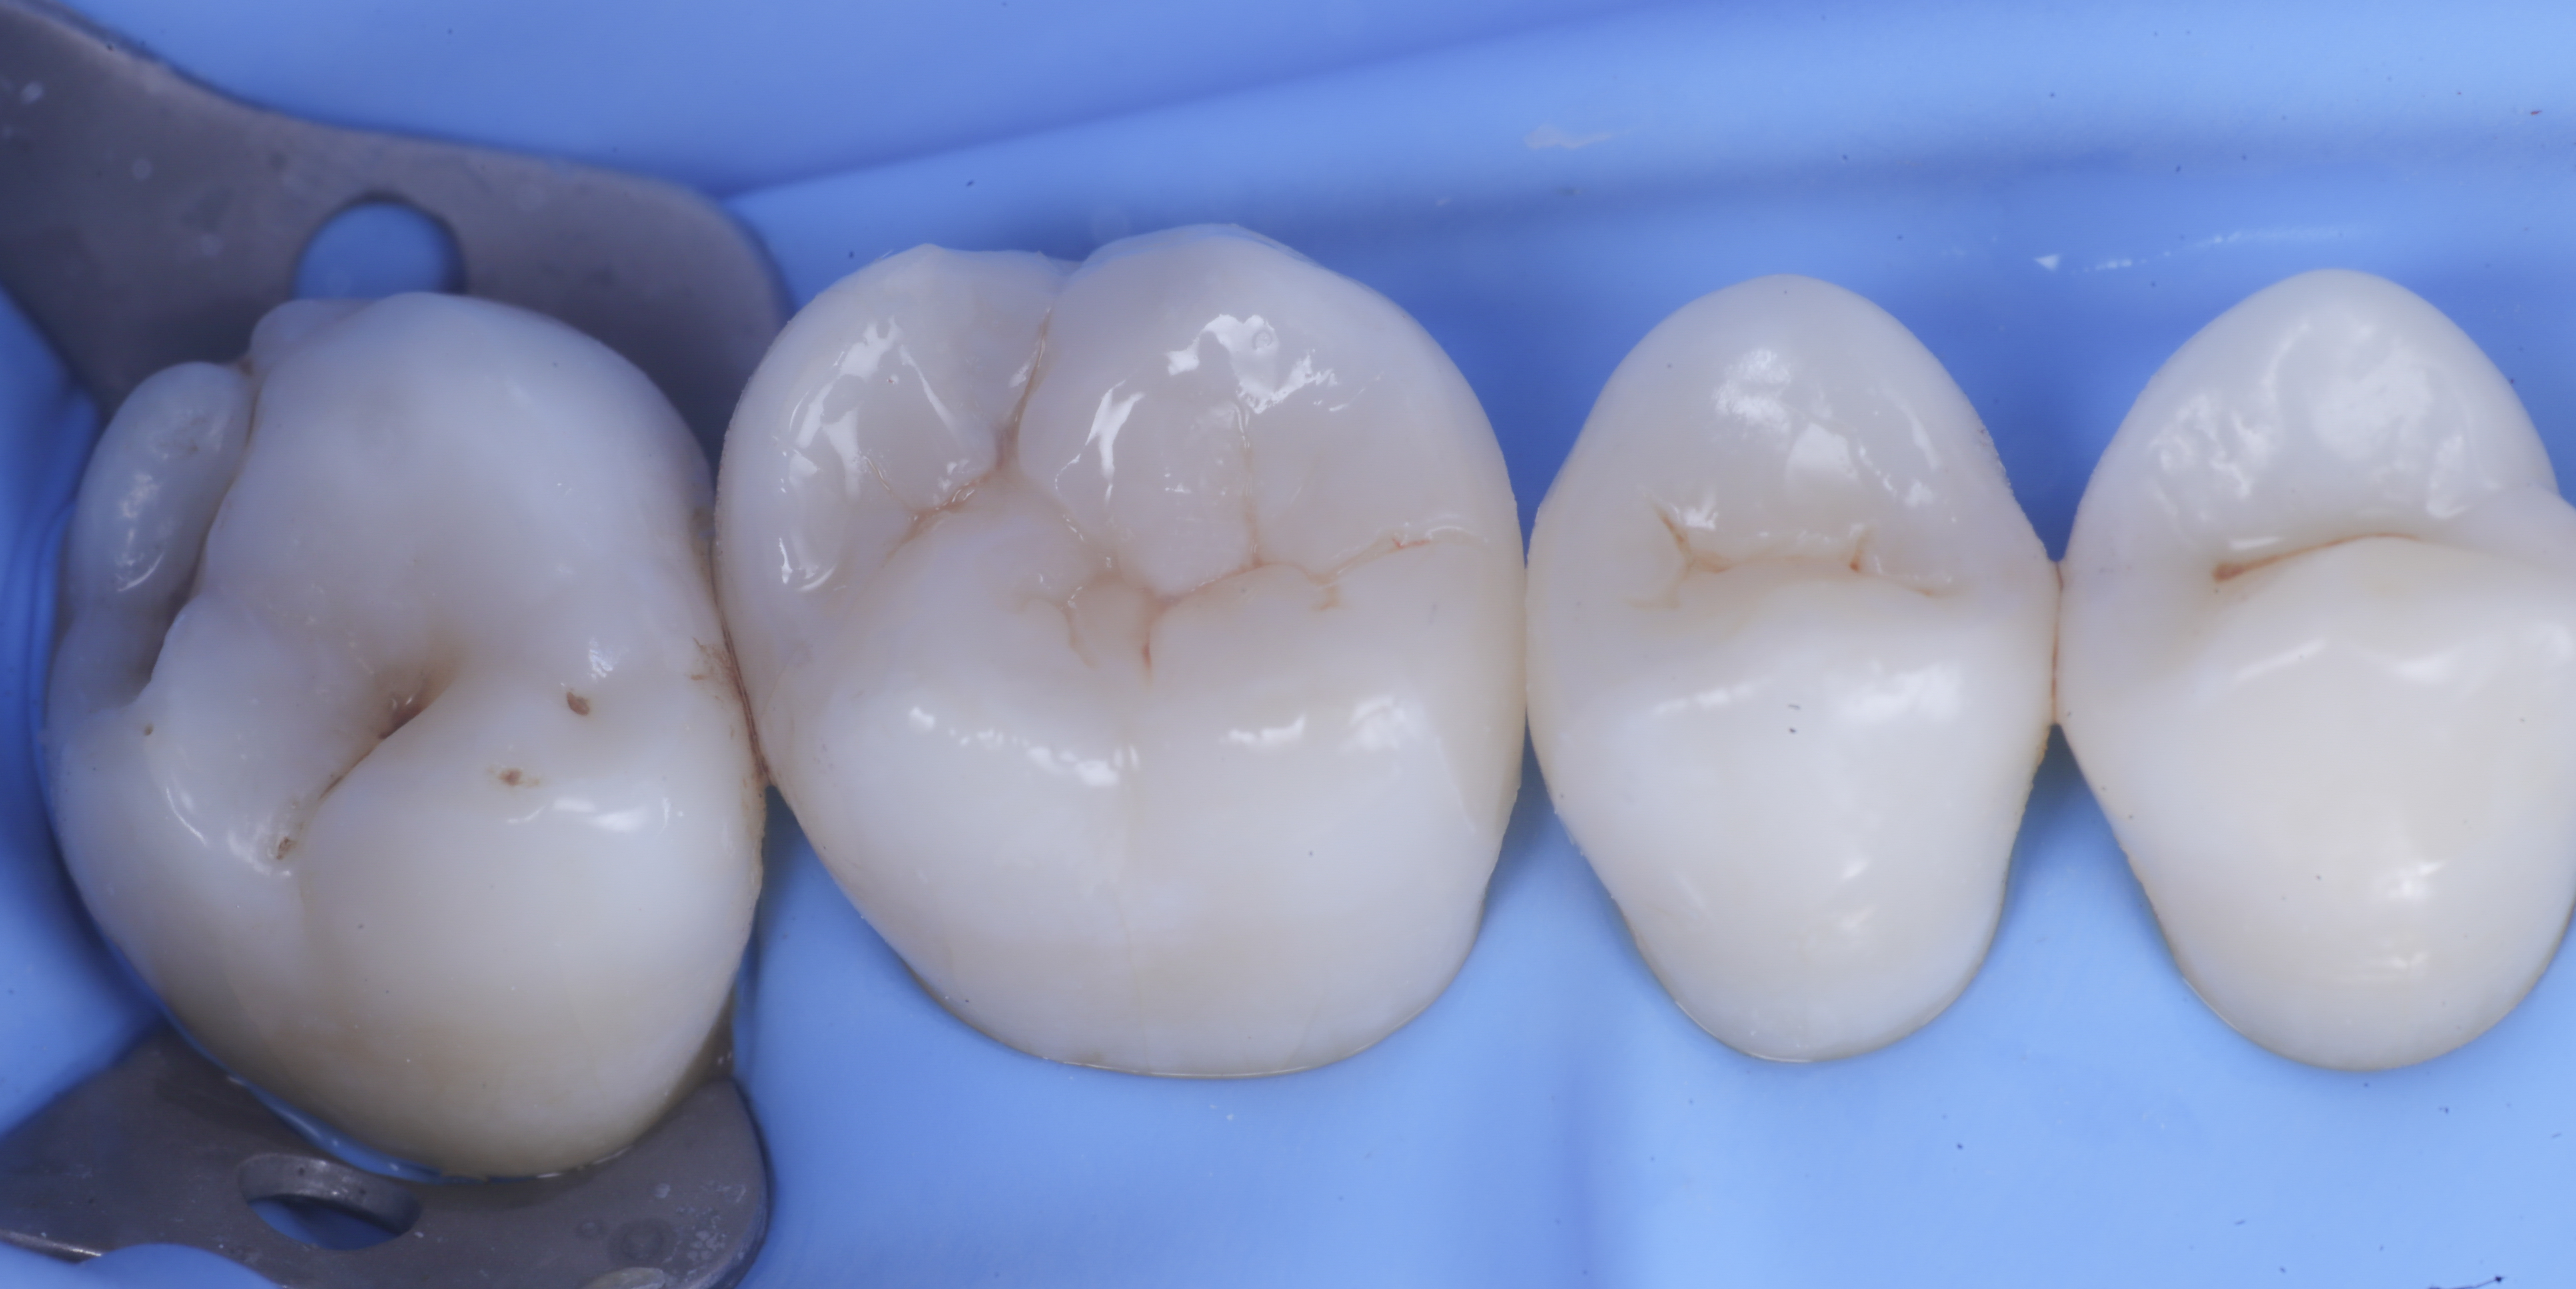

foto 6 Aspetto occlusale delle pareti interprossimali appena create

foto 7 Aspetto vestibolare delle pareti interprossimali appena create